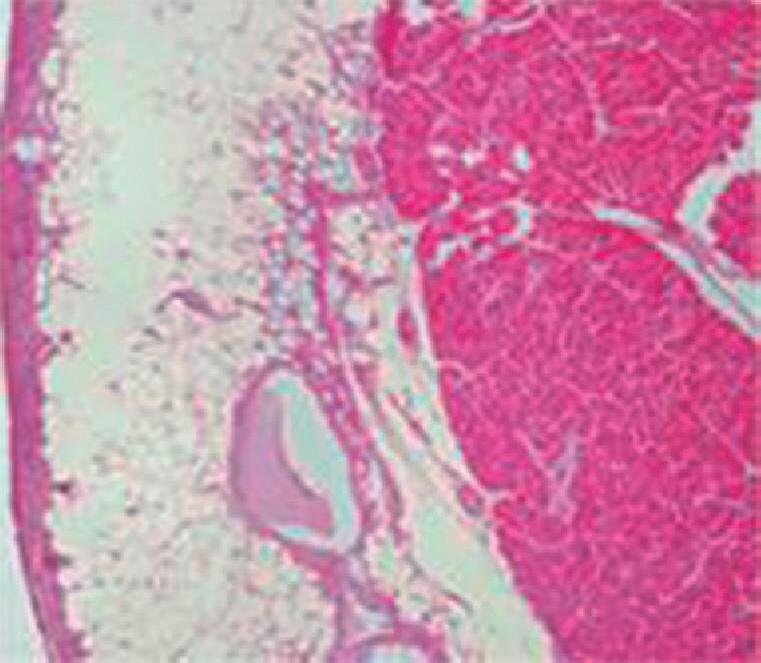

Fig. 2-31. Visão endoscópica de úlcera péptica gástrica (a,b); duodenal (c,d) com sangramento e substrato anatomopatológico do estômago com sangue e úlcera péptica (e,f). (Fonte: Arquivo do Departamento de Cirurgia-FCM/ unicamp.)